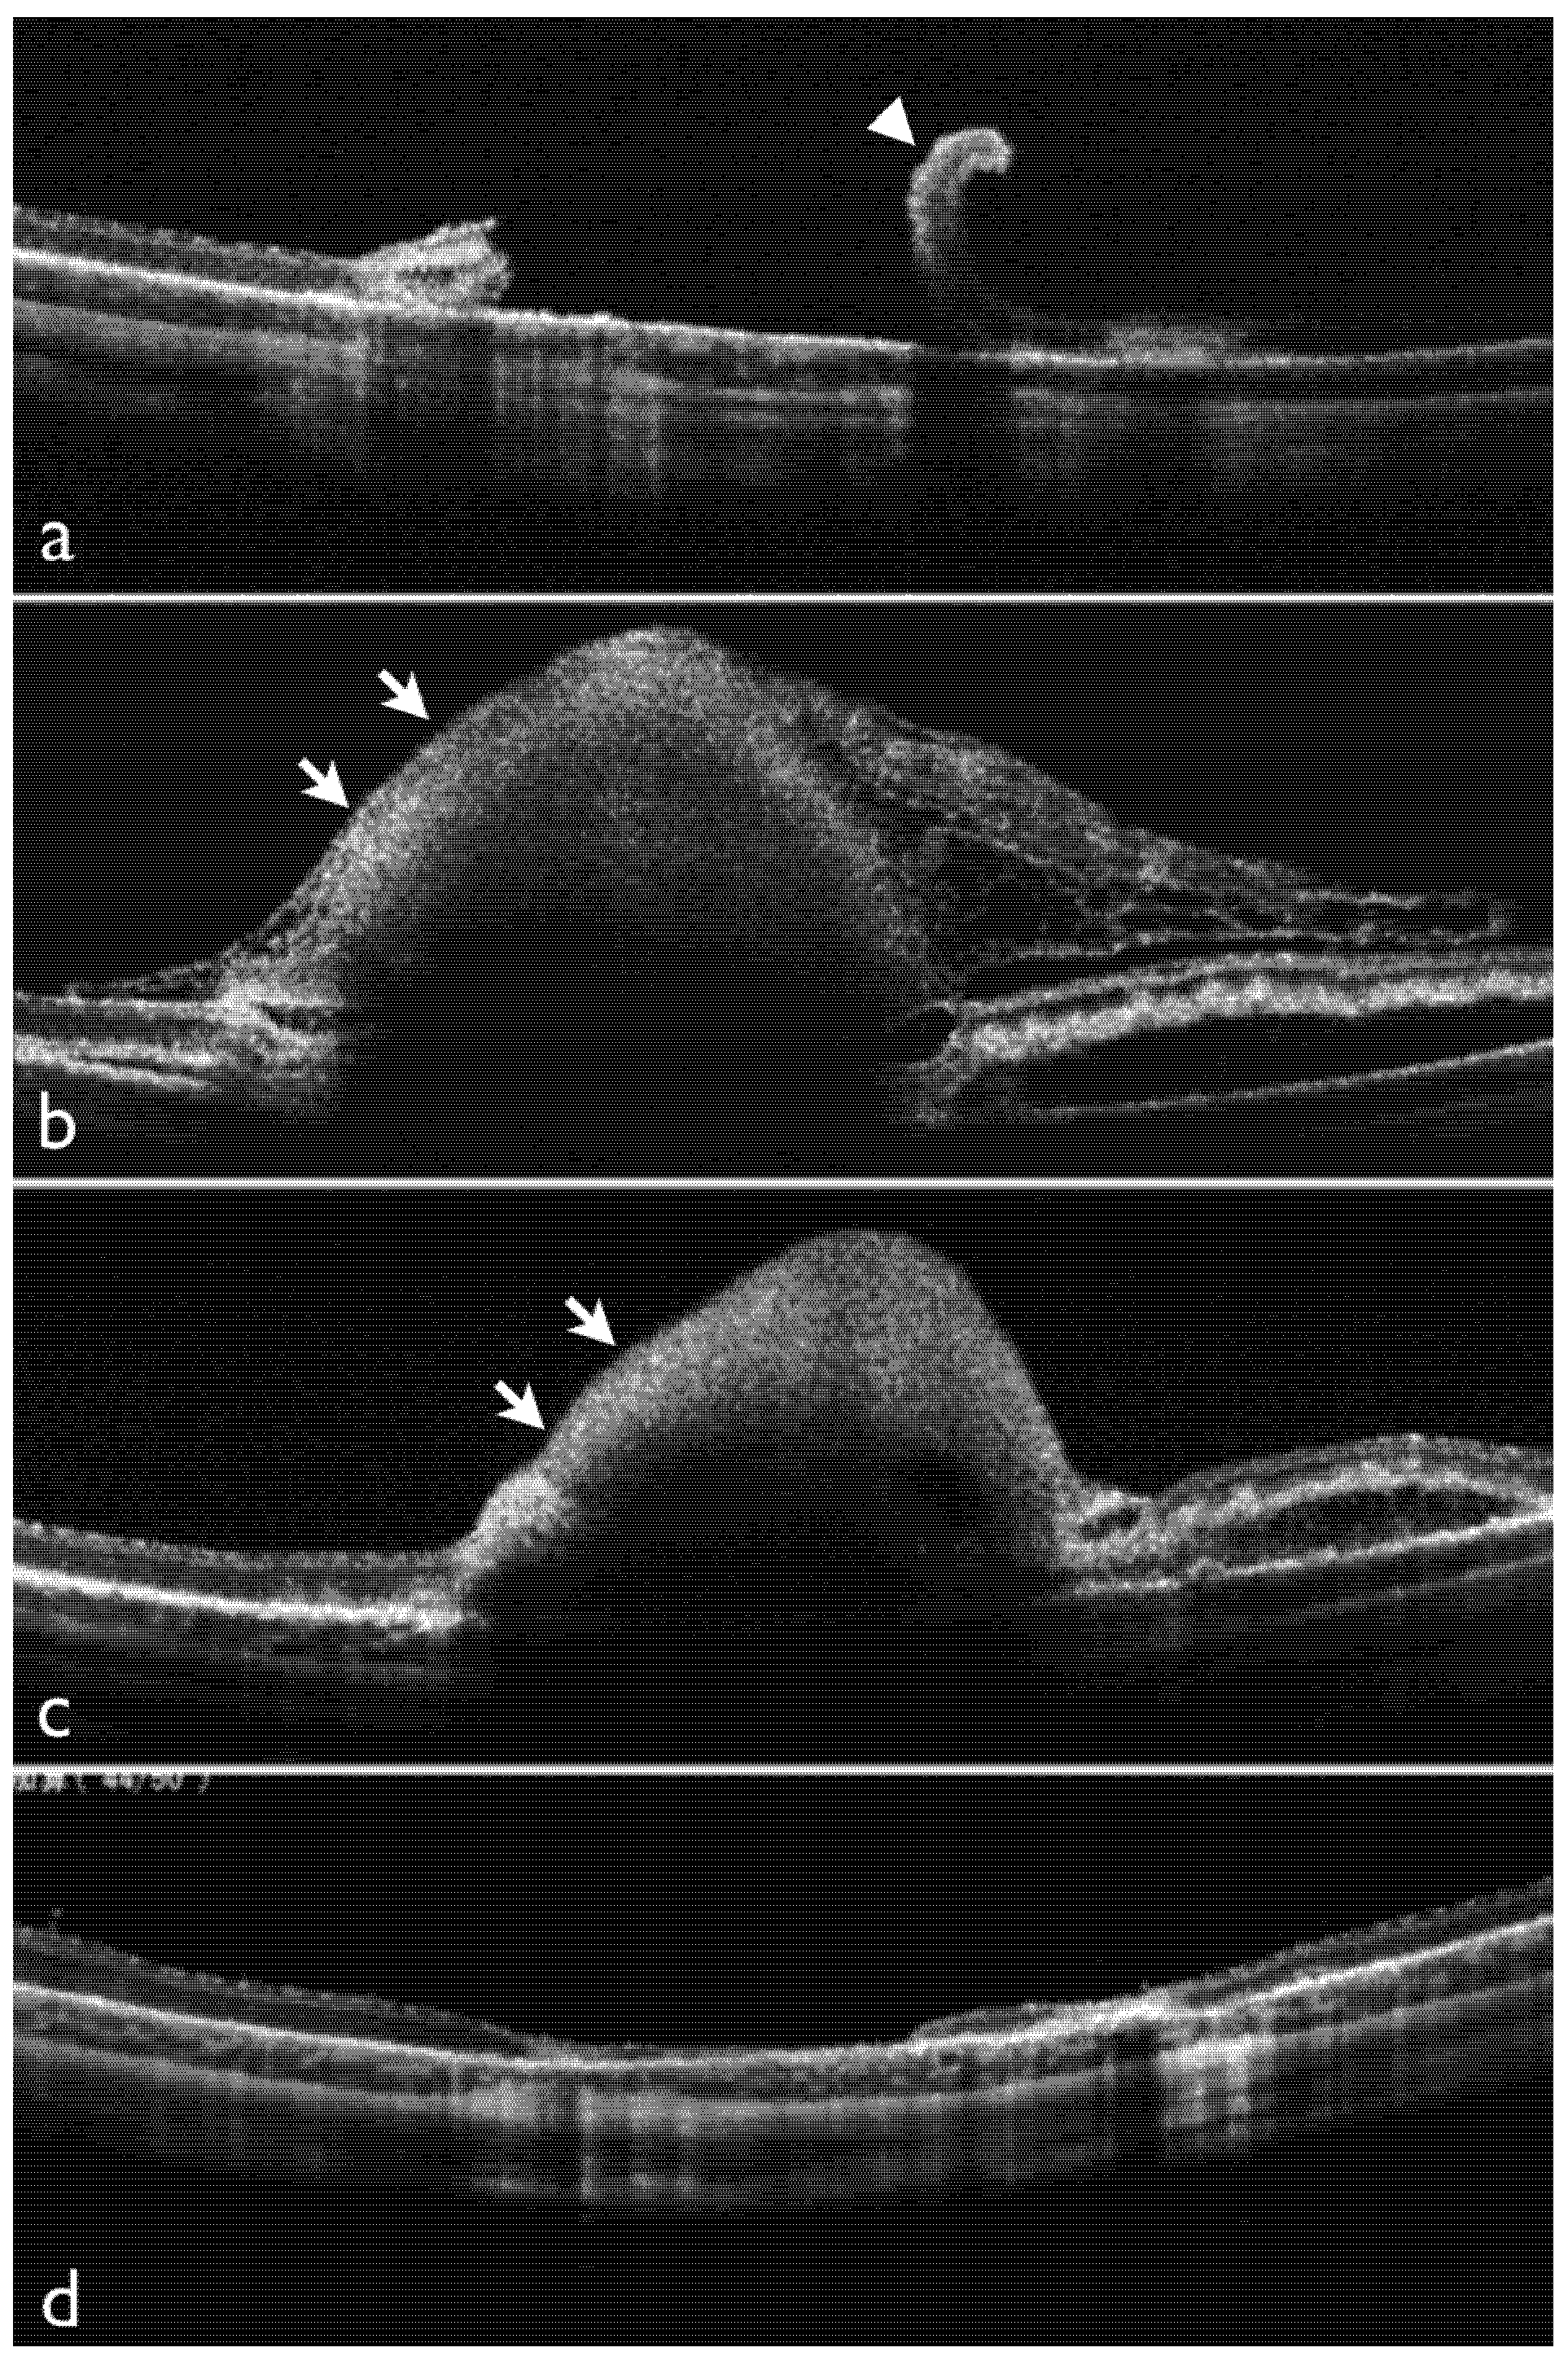

2.1. Effects of Dispersive OVD on Experimental Retinal Detachment Examined by OCT